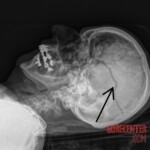

SLOVENIA – JANUARY 1, 2024 56-year-old woman from Slovenia was hit by a stray firework set off by a relative to celebrate the arrival of the year 2024. The rocket penetrated the woman’s right eye through the cranial cavity and damaged her brain. Despite immediate medical attention, she was pronounced dead.